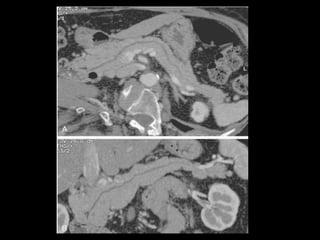

Protocolos de aquisição de imagens

A TCMD pancreática bifásica é considerada como a

técnica mais sensível tanto para a detecção como

para a classificação do estágio do adenocarcinoma

pancreático;

A TCMD pancreática bifásica consiste em uma fase

do parênquima pancreático(FP) e uma fase venosa

portal(FVP);

Fase portal: ↓ sensibilidade para T, mas ↑

sensibilidade para invasão vascular.

Os retardos de exame para a FP e a FVP podem ser

fixos ou individualizados;

Na primeira abordagem:

Retardo de exame de 40 e de 70 segundo para a FP e a

FVP respectivamente.

Preferência: retardo individualizado.

TCMD de 16 ou 64: 150 ml de contraste, razão de fluxo

de 8 ml/ s, 500 ml de água 20-30 min antes e 250 ml

imediatamente antes do exame;

Fase sem contraste: detectar calcificações e

determinar claramente a localização e extensão do

pâncreas.